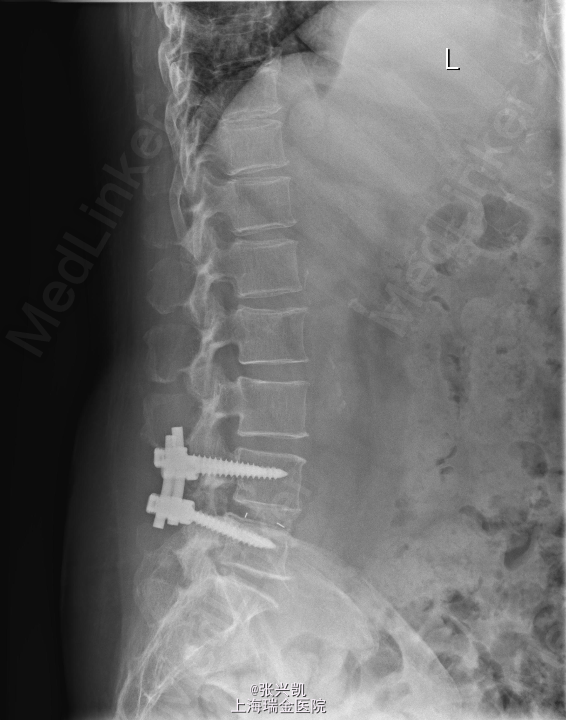

诊断:腰椎椎管狭窄L4-5 L4椎体滑脱 处理:腰椎后路减压复位融合内定术

随访:患者术后三月随访,下肢疼痛症状消失,可正常行走,腰部偶感酸胀感 讨论:针对术后有的患者有腰部酸胀不适感,有什么好的对症处理办法?